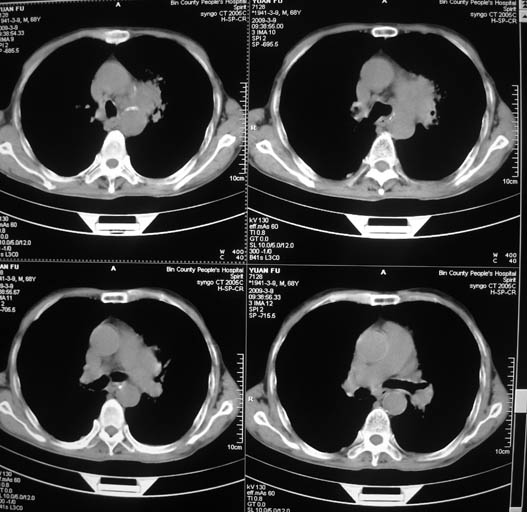

标题: CT18577:男,68岁,左肺占位。 [打印本页]

标题: CT18577:男,68岁,左肺占位。

男,68岁,左上肺占位,肺门淋巴结转移?

1)考虑左肺上叶尖段周围型肺癌并阻塞性肺炎,纵隔淋巴结转移。2)心包少量积液。

考虑左肺上叶尖段周围型肺癌并阻塞性肺炎,纵隔淋巴结转移.

1)考虑左肺上叶尖段周围型肺癌并阻塞性肺炎,纵隔淋巴结转移。2)心包少量积液

1)考虑左肺上叶尖段周围型肺癌并阻塞性肺炎,纵隔淋巴结转移。

2)心包少量积液。